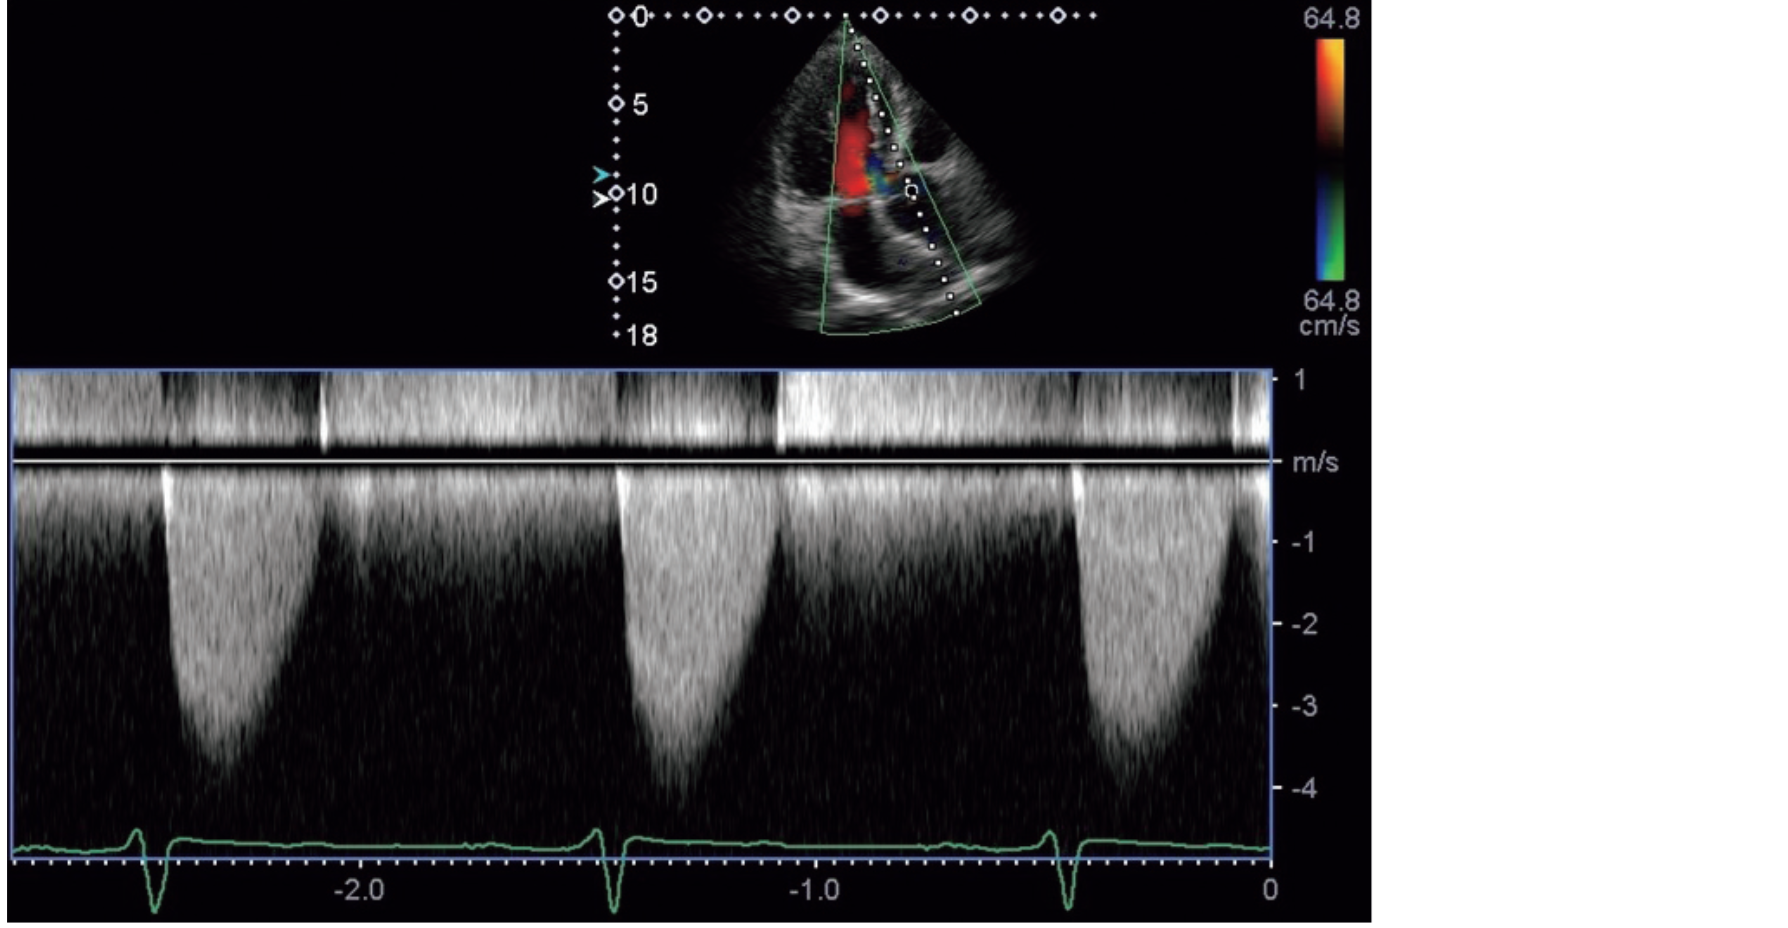

心尖部長軸断面の連続波ドプラ波形を示す。

狭窄前後の最大圧較差はどれか。

• 1. 16 mmHg

• 2. 32 mmHg

• 3. 64 mmHg

• 4. 80 mmHg

• 5. 96 mmHg